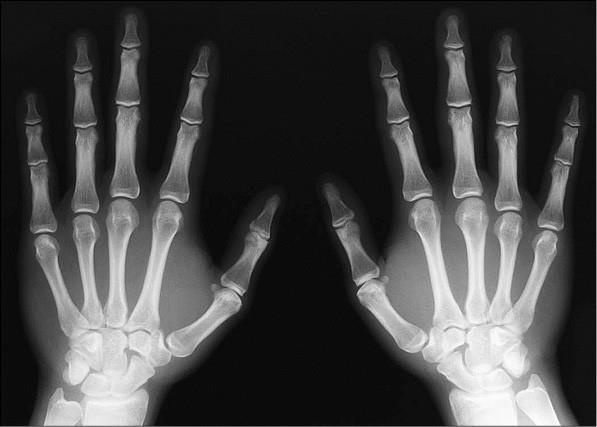

Иллюстрация к книге — 100 великих тайн медицины [i_060.jpg]

Лучевая болезнь возникает в результате сильного облучения, не менее 100 рентген